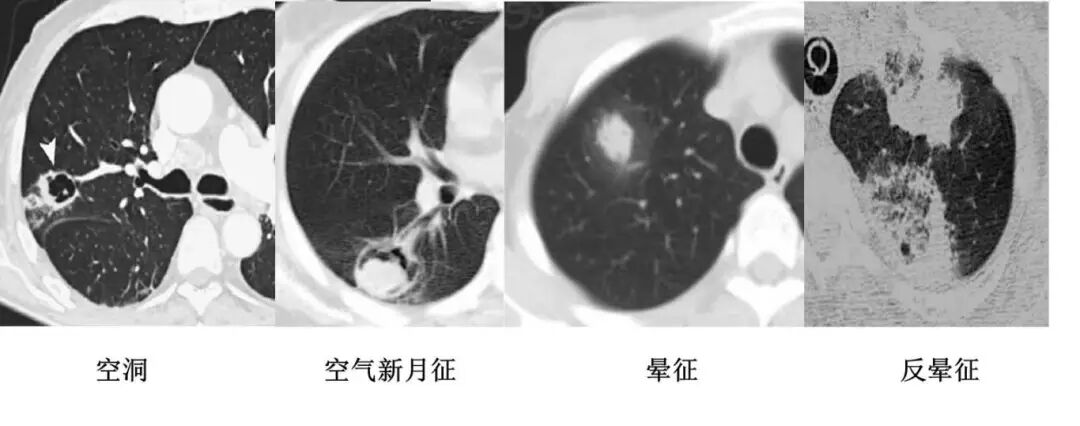

肺曲霉菌病

以胸膜为基底的楔形实变影;

充气支气管常属于正常管径范围。

空洞,空气新月征,晕征,反晕征

充气支气管常属于正常管径范围